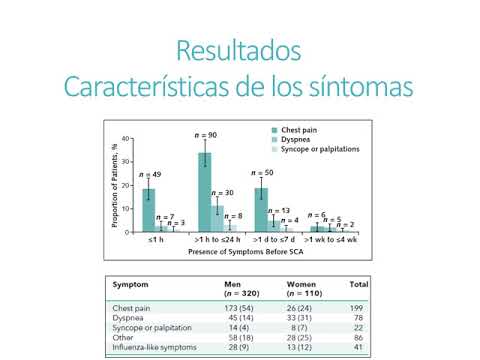

Muerte súbita en mujeres. Dra. María Eugenia Döppler. Residencia de Cardiología. Hospital C. Argerich. Buenos Aires